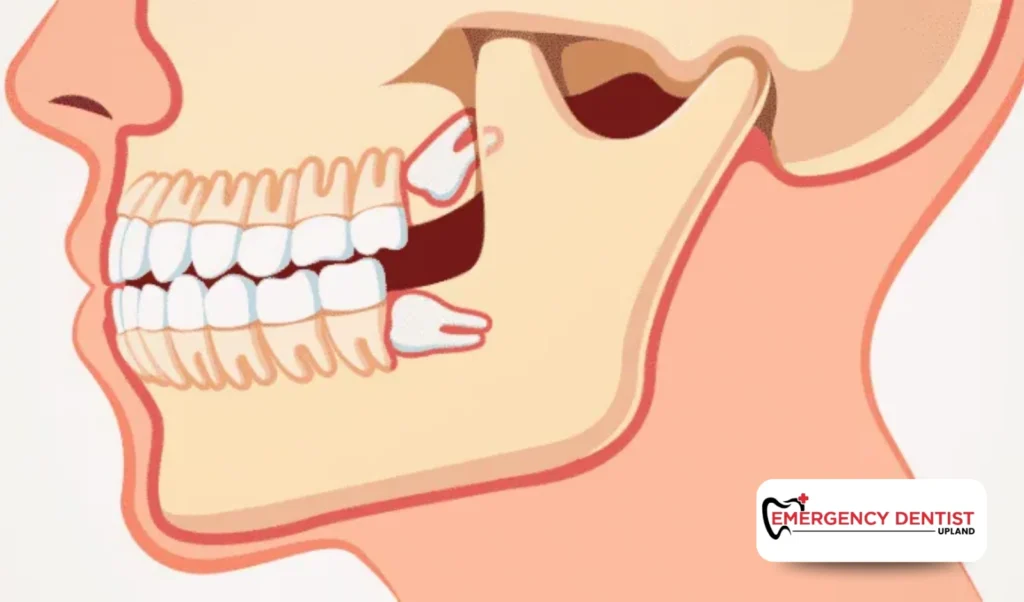

Some wisdom teeth grow straight and are fully erupted, making them easier to remove. Others may be angled, partially visible, or trapped beneath the gums, which increases the complexity of the dental procedure.

An impacted wisdom tooth does not fully break through the gums. This can lead to pressure, swelling, infection, or damage to surrounding teeth.